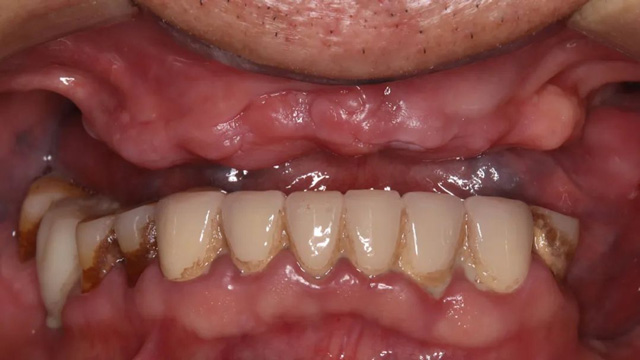

沈老师的上牙全部缺失

转机出现在2022年10月,沈老师的小儿子来四川大学华西第二医院儿科进修期间,在新桥口腔种了6颗牙,他对效果非常满意,便提议父亲也来成都试一试。此时的沈老师已经70岁,上半口牙已掉光,饮食非常不便。犹豫再三后,沈老师决定再搏一把。

经CBCT检查所见,沈老师的口腔情况比较复杂:下面原有的四颗种植牙只有一颗有牙冠,其余三颗种植体情况尚可,可以安装牙冠,上半口牙列缺失,牙槽骨里还埋着一个种植体。“这颗植体的位置没有骨板,不能受力,没有安装牙冠的条件。好在它位置在正中,不影响种植手术和牙冠修复。”